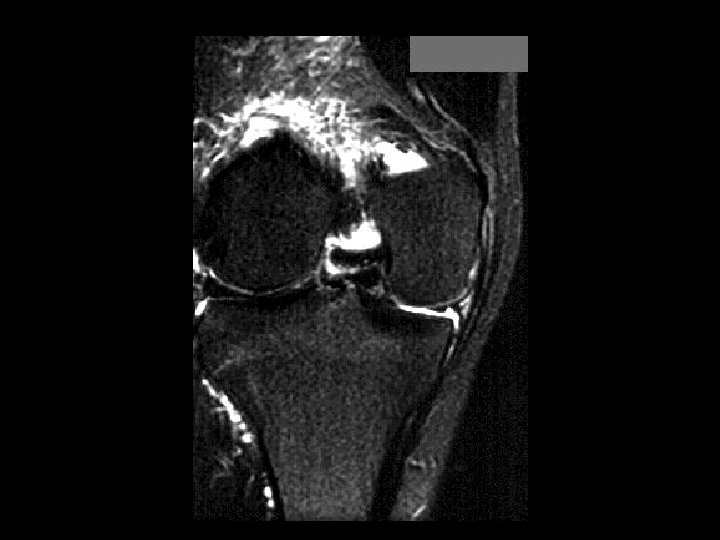

Bucket-Handle Tear • • Findings: – “double PCL sign” - torn meniscus BELOW normal PCL on sag view – Above ACL on cor view – Truncation of medial meniscus – Joint effusion Medial = 3 x lateral Locked knee ddx: – torn ACL, PCL – torn meniscus